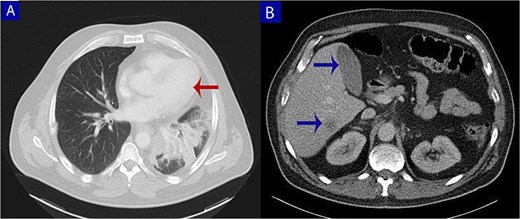

Contrast-enhanced computed tomography (CT) of the chest, abdomen, and pelvis. (A) Axial chest CT shows a lobulated mass (arrow) with heterogeneous enhancement centered at the left pulmonary hilum, invading adjacent bronchial and vascular structures. (B) Abdominal CT reveals multiple hypodense lesions in the liver (arrows), consistent with hepatic metastases.

A 49-year-old male with a 20-pack-year smoking history and occasional alcohol consumption presented with a painful, nodular skin lesion on his upper back. The lesion had been present for ~1 month and had progressively increased in size. Clinically, it appeared as a solitary, firm, erythematous nodule with central ulceration and overlying necrotic crust, measuring ~1.5 × 1 cm and surrounded by a violaceous inflammatory halo (Fig. 1). A partial excisional biopsy was obtained from the center of the lesion. Histopathological examination using hematoxylin and eosin staining revealed a poorly circumscribed, infiltrating tumor within the dermis. The tumor is composed of cords and nodules of atypical cells dissecting between collagen bundles, with focal areas of gland formation. The tumor extends into the subcutaneous adipose tissue and surrounding soft tissue in an irregular infiltrative pattern. The findings confirmed invasive adenocarcinoma (Fig. 2), prompting further evaluation to assess for metastatic spread. Contrast-enhanced computed tomography (CT) of the chest, abdomen, and pelvis demonstrated a lobulated mass with heterogeneous enhancement centered at the left pulmonary hilum, invading adjacent bronchi and vascular structures (Fig. 3A). Multiple hypodense lesions in the liver were consistent with hepatic metastases (Fig. 3B). Additionally, numerous lytic bone lesions were noted involving the ribs, vertebral bodies, sternum, and right pubic bone, indicating widespread skeletal metastases.A positron emission tomography–computed tomography (PET-CT) scan was not performed due to lack of availability in Syria. Bronchoscopy revealed complete obstruction of the left upper lobe bronchus, and a biopsy was obtained from the lesion. Histopathological examination demonstrated features consistent with invasive high-grade HAC, characterized by large polygonal cells with abundant eosinophilic cytoplasm and prominent nucleoli, resembling HCC morphology (Fig. 4). To further support the diagnosis, immunohistochemical staining was performed. The tumour cells showed strong positivity for CK7, HepPar-1, and CK19 (Fig. 5), and were negative for TTF-1, Napsin-A, p40, alpha-fetoprotein (AFP), and Glypican-3. Serum AFP level was within normal limits. This immunoprofile supports the diagnosis of HAC of pulmonary origin. In addition, immunohistochemical staining for HepPar-1 was performed on the biopsy from the subcutaneous metastasis, which also showed positive staining (Fig. 6). This finding further supports the lung as the primary site of the hepatoid carcinoma, given the matching immunophenotype between the primary lung tumour and the cutaneous metastasis.

Radiologically, the largest mass was centered in the left upper pulmonary hilum, while the hepatic lesions were smaller and more scattered—consistent with secondary liver metastases rather than a primary hepatic tumor.